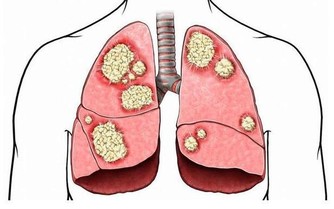

但傷害他們的,不是血管出血破裂,而是來自心臟的血栓阻斷了血液流通。

但隨著技術進步,新型介入性動脈­機械取栓法,

不僅將治療黃金期延長至12小時,更能有效地取出血栓,

前提是,病患大腦­不能全無側枝循環。